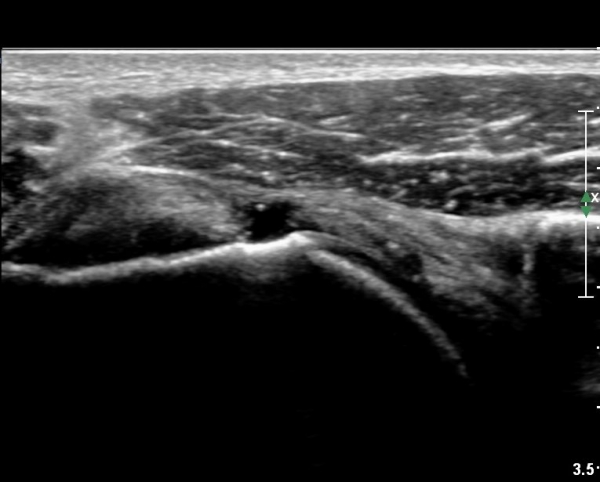

°ß°©ÇÏ±Ù°Ç »óºÎ Á¾´Ü¸é°Ë»ç¿¡¼­ °ß°©ÇϱٰǠ ÆÄ¿­ÀÌ ¶Ñ·ÈÇÔ(»çÁø 4, 5).

°ß°©ÇÏ±Ù°Ç ÁߺΠÁ¾´Ü¸é°Å»ç¿¡¼­ ÈûÁÙÀÌ ¾ã°Ô º¸¿© ÆÄ¿­·Î ÃÊÁ¤µÊ(»çÁø 7).